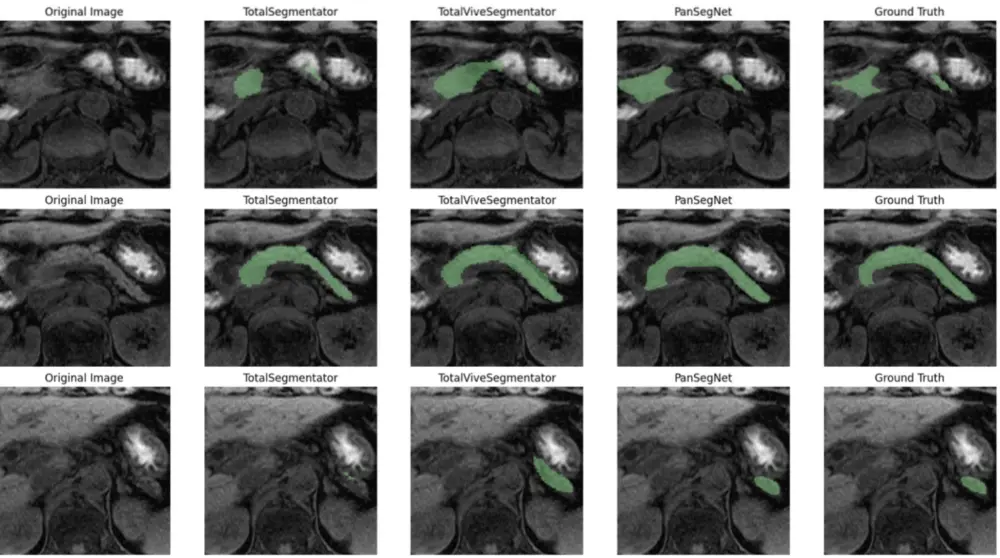

大規模腹部MRIデータの膵臓セグメンテーションモデルに関する基礎的な定量分析を行っています。この研究をベースとして、微視的な膵ボリュームの経時的変化の分析に取り組み、臨床に有用な知見の抽出を目指しています。